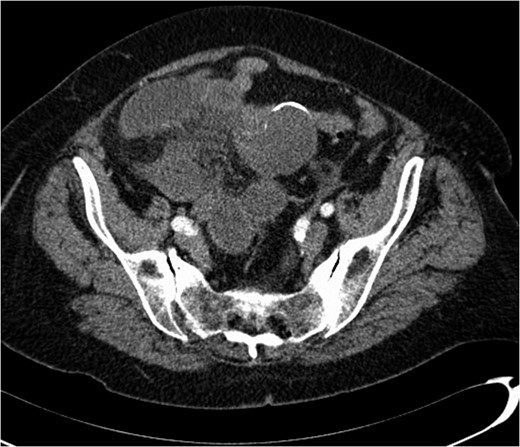

A 74-year-old female, with a background history of hypertension and hypothyroidism, presented to the emergency department with a 6-h history of sudden onset generalized abdominal pain. The pain was colicky in nature, associated with nausea and refractory to analgesia. Examination revealed tenderness in the right upper quadrant and epigastrium. Blood tests were normal except for a mild neutrophilia (7.5 × 109/l) and lactate of 2.5 mmol/l. A computed tomography (CT) scan of her abdomen and pelvis was performed which showed abnormal loops of small bowel along the right side of the abdomen with mesenteric fat stranding. A partially calcified structure was noted lying medial to the loops of bowel (Figs 1 and 2). The patient proceeded to have an explorative laparotomy performed. Intraoperative findings revealed an ischaemic loop of small bowel wrapped around a mass in the mesentery adjacent to the sigmoid colon (Fig. 3). The patient underwent a partial small bowel resection with primary anastomosis and en-bloc resection of the mass with the formation of an end colostomy. The final histological revealed a 6 × 4 × 4 cm cystic colonic duplication cyst separate but adjacent to the sigmoid colon. The inner lining of the cyst revealed mucinous epithelium, with mucin contained within. The wall of the cyst was sclerotic with occasional lymphoid aggregates, smooth muscle and neurovascular bundles (Fig. 4). The patient made a good recovery and was discharged home.

Haemolysin and eosin stain showing occasional lymphoid aggregates, smooth muscle and neurovascular bundles within the duplication cyst.